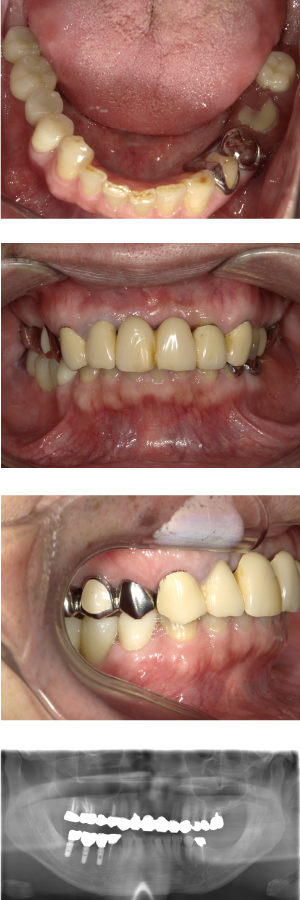

60代 女性 全顎 インプラント サイナスリフト等

| 年代・性別 | 60代・女性 |

| 主訴 | 上顎の入れ歯が割れた。リンゴやおかきを食べられるようになりたい。 |

| 部位 | 右上④3②・左上②3④5⑥のブリッジ |

| 治療期間 | 2年 |

| 費用 | ¥2,447,500(税込) |

| 副作用・リスク |